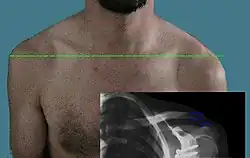

Die Ursache einer traumatischen Luxation ist meist ein indirektes Trauma, beispielsweise ein Sturz auf den Arm oder ein Aufkommen mit dem Bein[2] bei einem Sprung. Am häufigsten ist die Schulterluxation, die mehr als 50 % aller traumatischen Luxationen ausmacht, gefolgt von der Ellenbogenluxation. Auch Luxationen am Knie oder Sprunggelenk treten häufig auf.[3] Fast alle Gelenke können betroffen sein (auch Kieferluxation). An den Fingergelenken führen meist Überstreckverletzungen zur Luxation, häufiger beim Handball und Volleyball. Die Schultereckgelenk-Luxation entsteht am häufigsten beim Fahrradsturz (s. Bild). Selten kann auch direkter Zug eine Luxation auslösen, wie bei der kindlichen Radiuskopfluxation durch Zug am gestreckten pronierten Arm (Pronatio dolorosa Chassaignac).

Bei der Untersuchung bestehen eine Schonhaltung mit Funktionsverlust und Schmerzen, gelegentlich eine Schwellung und ein Bluterguss. So genannte „sichere“ Luxationzeichen sind eine sichtbare Deformität, eine erkennbare leere Gelenkpfanne und abnorme Lage des Gelenkkopfes (an der Schulter oft sichtbar) und eine federnde Fixation. Aber auch bei einer scheinbar intakten Gelenkfunktion kann eine Luxation vorliegen.

Beweisend sind Röntgenaufnahmen in zwei Ebenen, wobei seltene Formen (wie die hintere Schulterluxation) und kindliche Luxationen auch dabei schwer zu erkennen sind. Dann hilft eine Computertomografie (CT), Kernspintomographie (MRT) oder Arthrografie (besondere Röntgentechnik mit Einbringen eines Kontrastmittels in das Gelenk). Bei Kindern sind Luxationen im Ultraschall gut darstellbar.